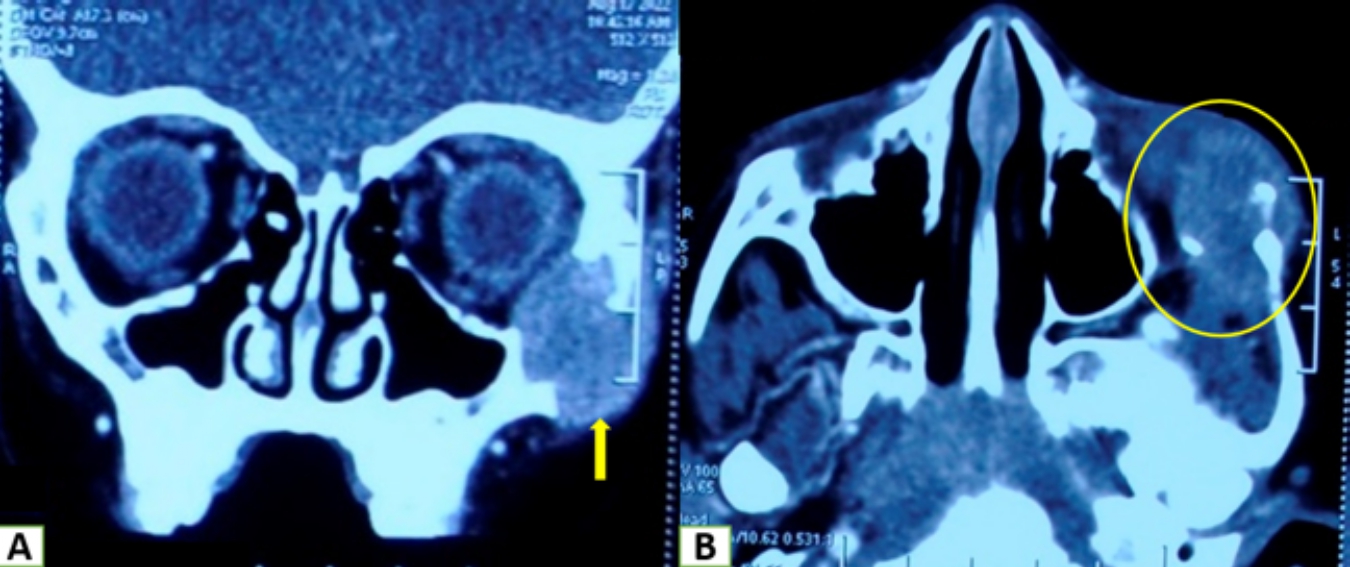

• Coronal and axial views are displaying a lytic expansile lesion involving the body of left zygoma and adjacent anterior zygomatic arch with cortical destruction.